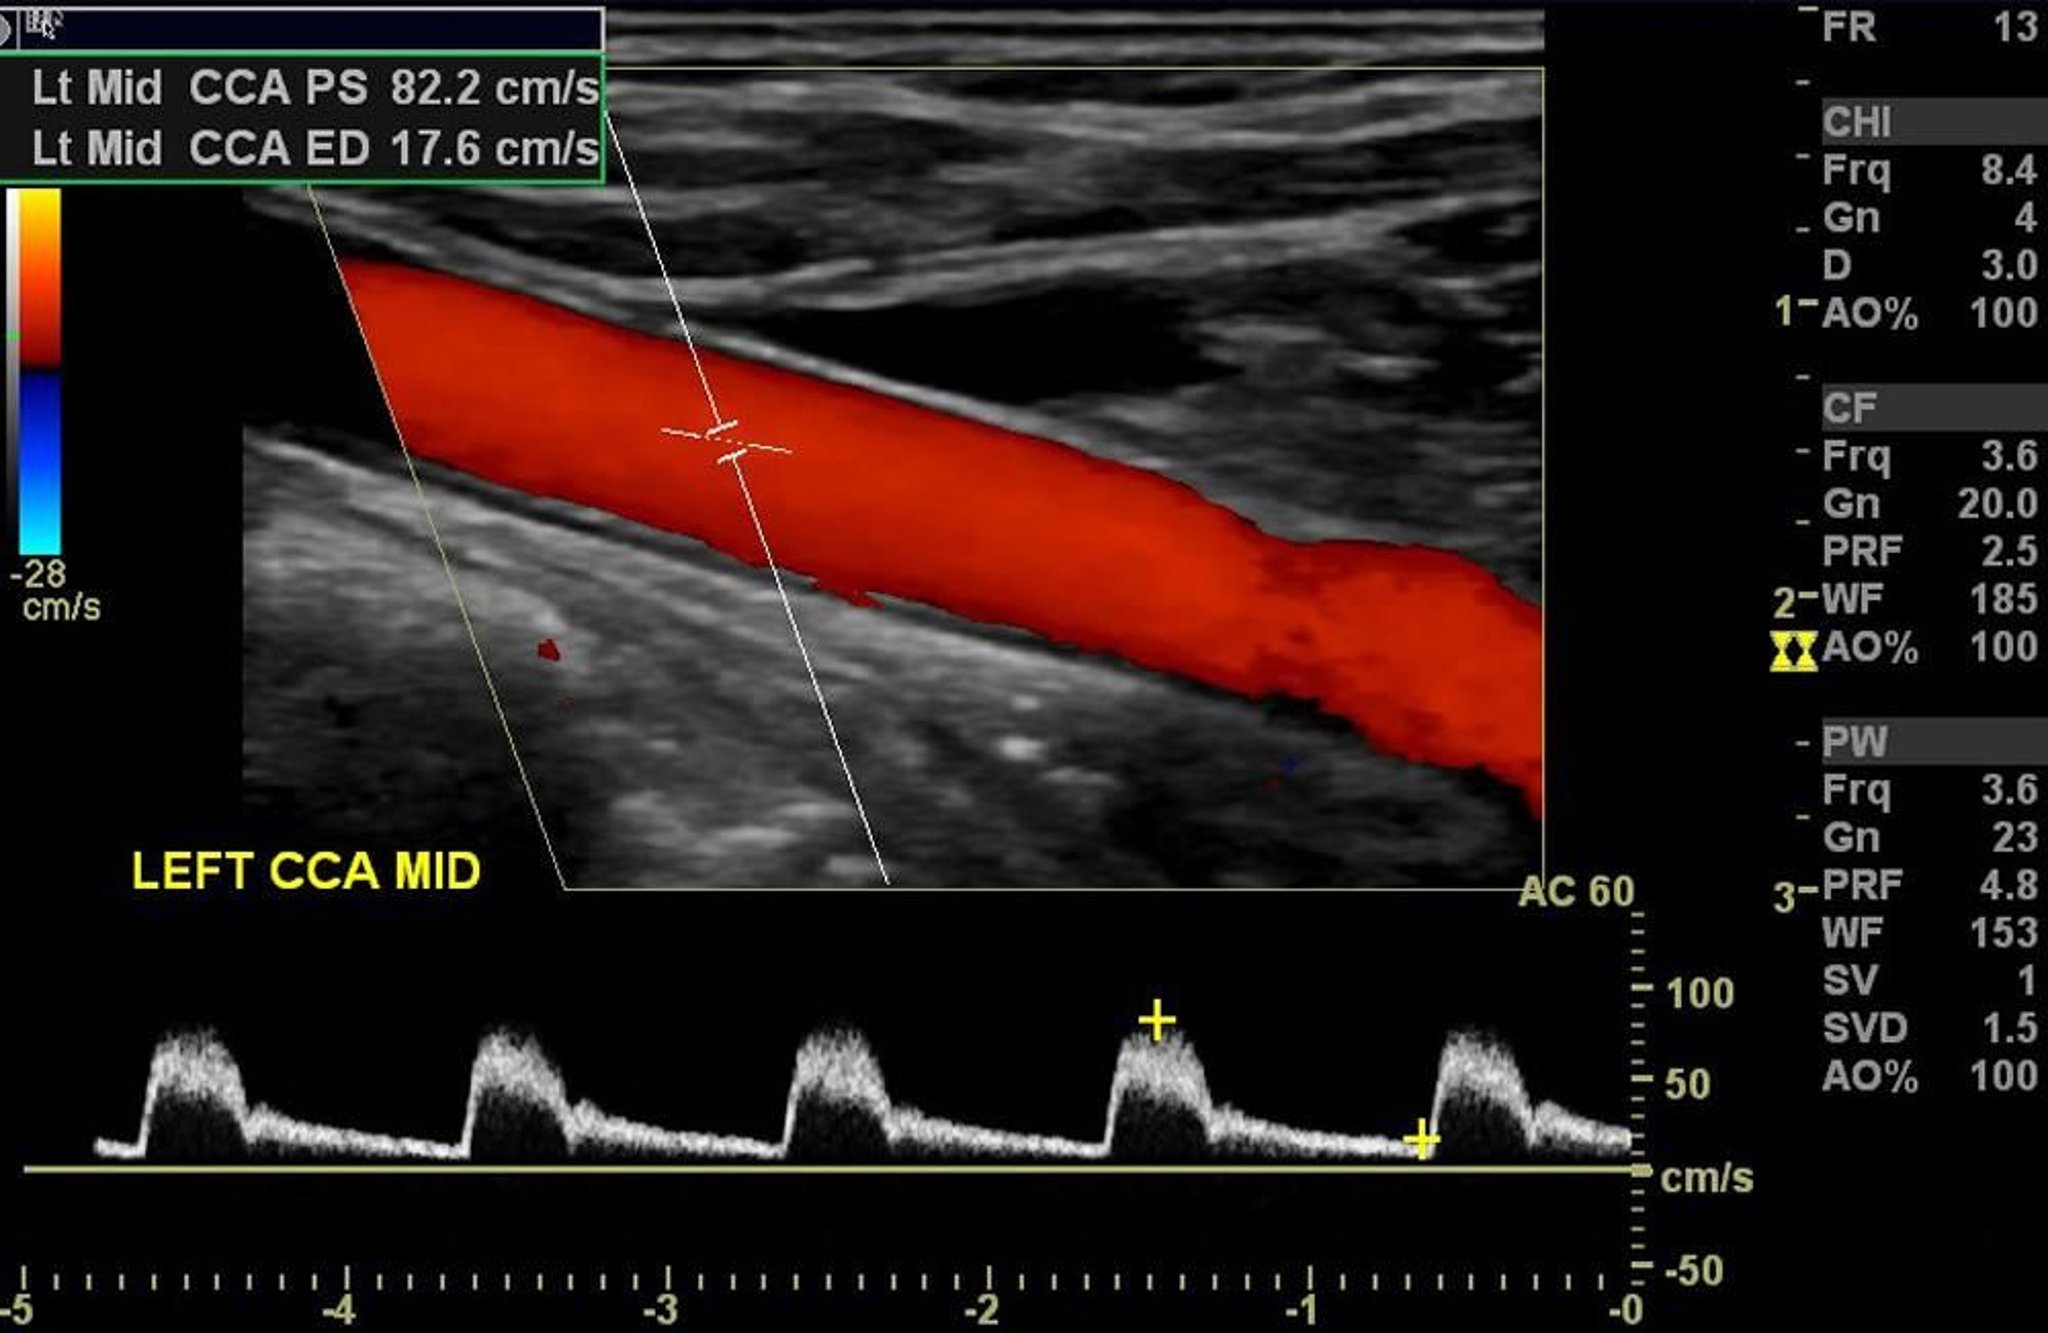

Color Doppler ultrasound of the left carotid artery shows normal arterial flow without significant stenosis.

Image courtesy of Hakan Ilaslan, MD.

Spectral Doppler ultrasound displays blood flow information as a graph with velocity on the vertical axis and time on the horizontal axis. Specific velocities can be measured if the Doppler angle (the angle between the direction of the ultrasound beam and the direction of blood flow) can be determined. Velocity measurements and the appearance of the spectral Doppler tracing can indicate the severity of vascular stenoses.

Duplex Doppler ultrasound combines the graphic display of spectral ultrasound with the images of B-mode.

Color Doppler ultrasound converts the Doppler blood flow information into a color image with blood flow in color; it is displayed on a gray-scale anatomic ultrasound image. Direction of blood flow is indicated by the shade of color (eg, red for blood flow toward the transducer, blue for blood flow away from the transducer). Average blood flow velocity is indicated by the brightness of the color (eg, bright red indicates high-velocity flow toward the transducer; dark blue indicates low-velocity flow away from the transducer).